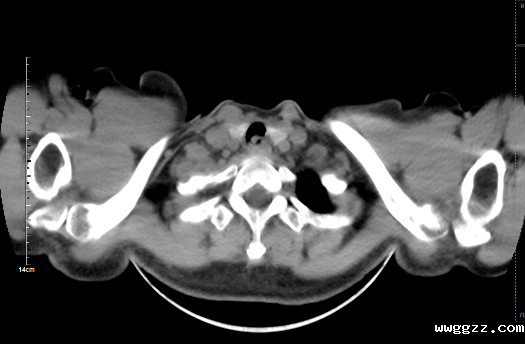

患者李女士近期外出劳作时有饮生水习惯,1月前开始出现咽痛、咳嗽、声音嘶哑及喘促症状,就诊入院后行胸部增强CT检查,提示支气管上段占位性病变,建议活检。经肺病科与麻醉科团队评估,决定在全麻下为患者实施电子支气管镜检查。当支气管镜进入声门后,在支气管上段发现一活动异物,继续推进镜体,可见一活体蚂蟥正牢牢吸附在支气管上段管壁上。